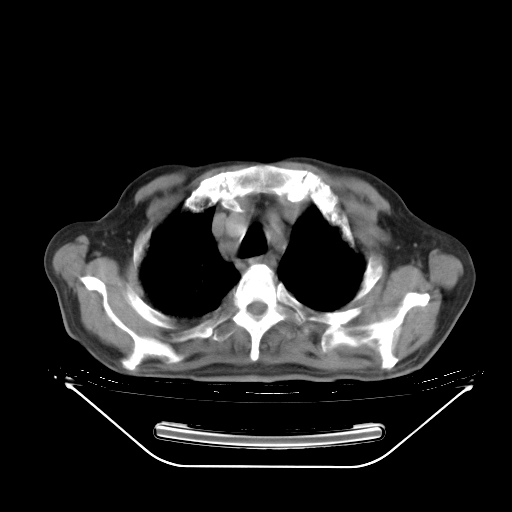

今天复查肺部CT,发现双肺广泛磨玻璃样改变。所以我把3月19日和5月9日相隔50天的肺部CT上传。请大家会诊。

2009年3月19日肺部CT片。

5月9日肺部CT(在4月27日齐鲁医院肺部CT描述部分肺组织磨玻璃样改变,12天后肺组织广泛磨玻璃样改变)